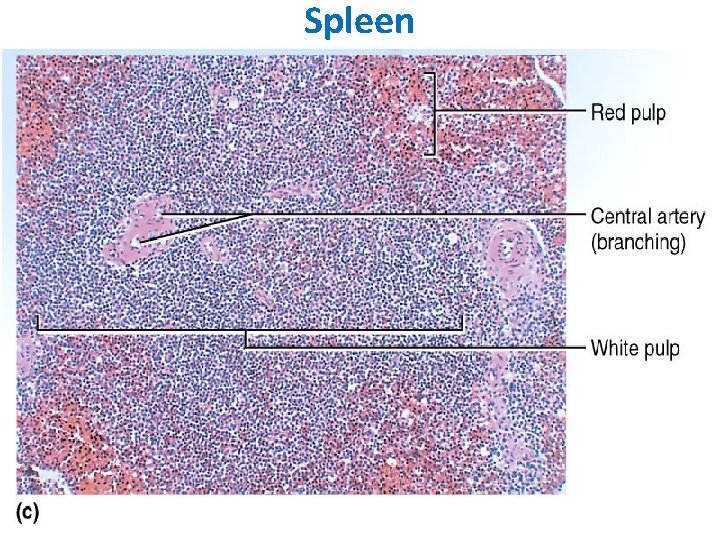

SPLEEN The largest of the lymphoid organs. Splenic pulp is composed of many erythrocytes, leukocytes, and macrophages, as well as a variety of blood vessels, all suspended within a meshwork of mesenchymal reticular cells and fibers. White pulp consists of the lymphoid tissue surrounding each of the many central arteries; it has 2 major components. The sleeves of lymphoid tissue immediately surrounding each central artery are called periarterial lymphatic sheaths (PALS). These contain mainly T lymphocytes and constitute the T-dependent regions of the spleen. Surrounding each PALS, or appended to one side, is the second component, the peripheral white pulp (PWP). PWP contains mainly B lymphocytes and usually includes a typical secondary lymphoid nodule with a germinal center.

Red pulp makes up most of the spleen and also has 2 major components: the red pulp cords and the splenic sinusoids that lie between them. The red pulp (Billroth’s) cords are irregular sheets of reticular connective tissue that branch and anastomose to surround the sinuses. In addition to reticular cells and fibers, the cords contain many cell types, including all the formed elements of blood, dendritic cells, macrophages, plasma cells, and lymphocytes. Splenic sinusoids differ from common capillaries: the lumen is wider and more irregular; there are 2 -3 - m spaces between the lining endothelial cells; and there is a sparse, discontinuous basal lamina that is composed largely of reticular fibers arranged in bands that run roughly perpendicular to the length of the vessel. The marginal zone forms a border between the white and red pulp; it consists of a moatlike arrangement of blood sinuses and loose lymphoid tissue containing few lymphocytes.